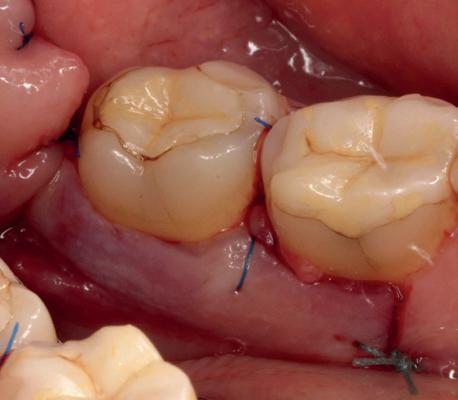

In afbeeldingen 4a-c is het resultaat drie maanden na het plaatsen van het implantaat te zien. De genezing is volledig en de verwijzer kan de suprastructuur vervaardigen (afbeelding 4a-4c).

In afbeeldingen 5a-d is de implantaatkroon 37 te zien, twee jaar na plaatsing. Op de röntgenfoto is herstel van zowel corticaal als spongieus bot te zien. (De CB-CT was vervaardigd in verband met implantologische indicatie in het naastliggende gebied).